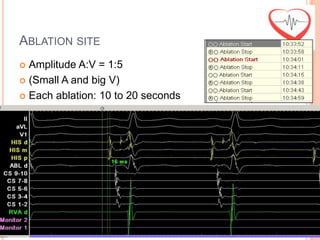

ABLATION SITE

 Amplitude A:V = 1:5

 (Small A and big V)

 Each ablation: 10 to 20 seconds

ABLATION SITE  AmplitudeA:V = 1:5  (Small A and big V)  Each ablation: 10 to 20 seconds

ABLATION SITE  Eachablation: 10 to 20 seconds  Amplitude A:V = 1:5  (Small A and big V)